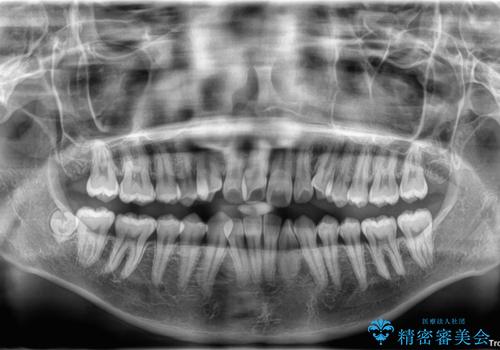

- 「前歯のデコボコ(叢生)をきれいに整えたい」とのことでご来院されました。

上下の正中(真ん中のライン)もずれることなく、バランスの取れた美しい歯並びに。笑顔に自信を持てる仕上がりとなりました。